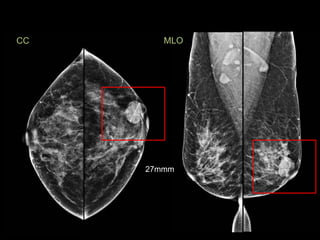

MLO

CC

27mmm

Birads 4 - Sospechoso de

malignidad

Carcinoma mucinoso